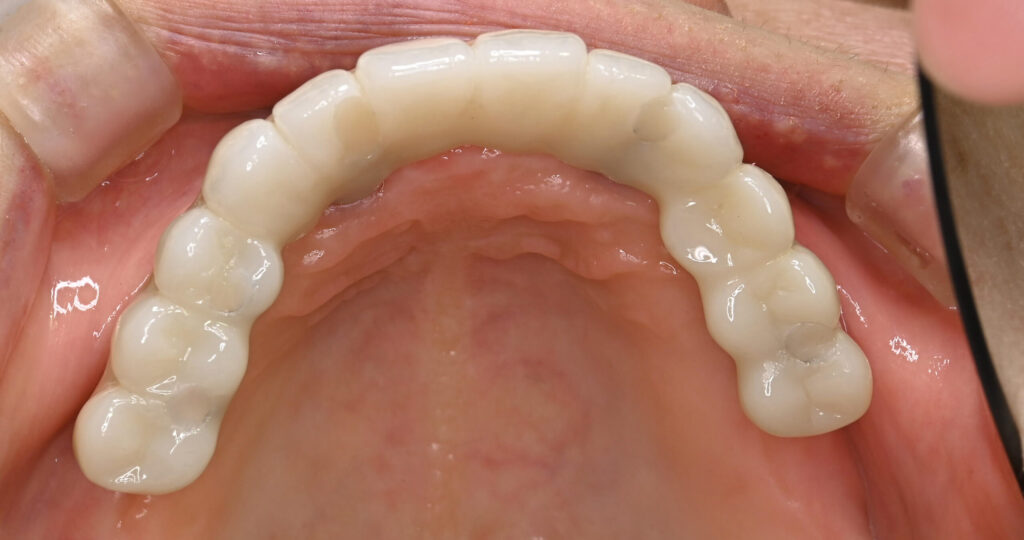

After

治療期間・回数

約6ヶ月・約6回

費用

23,100,000円

治療のリスク

外科手術が必要になるため、患者様に体力的な負担がかかる。